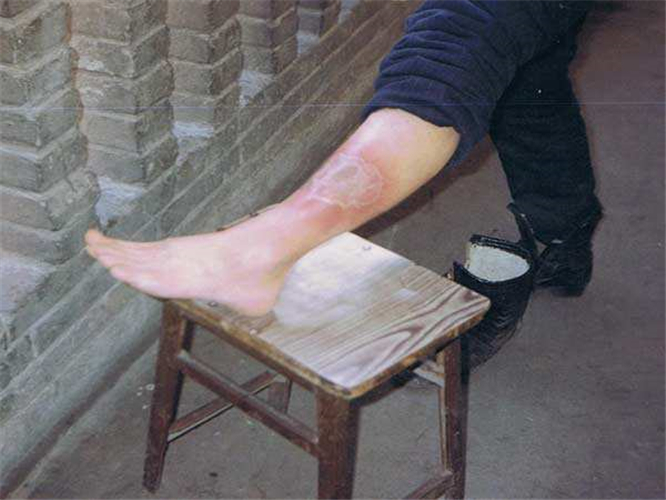

左小腿靜脈炎

左小腿靜脈炎症狀

治療下肢血栓性淺靜脈炎

足部淺表型靜脈炎